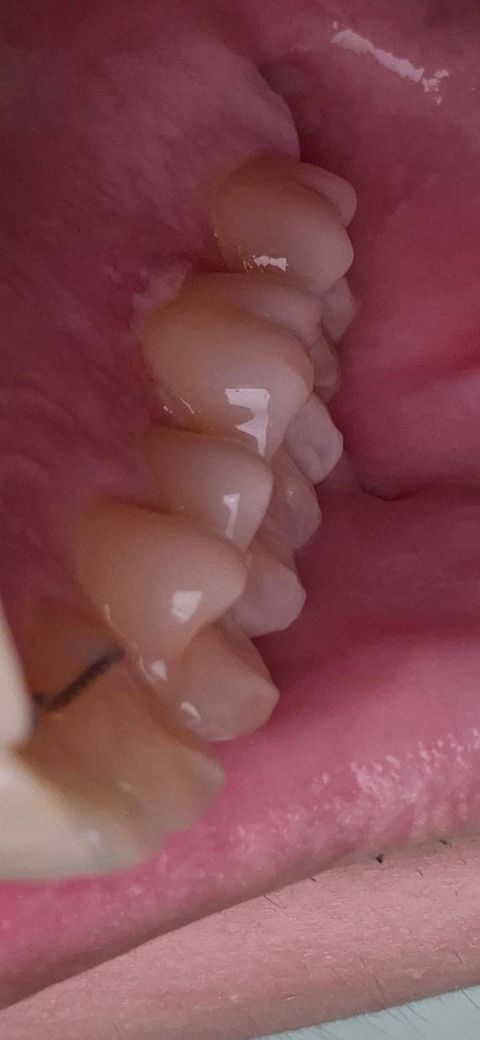

잇몸에 하얗게 무언가가 생겼는데 아파요

잇몸에 하얗게 뭔가가 생겼는데 밥을먹거나 만지면 아파요 무엇인지 궁금합니다 위험한걸까요? 가만히있으면 안아픈데 밥먹을때 불편합니다ㅠ

잇몸에 염증이 생긴 것으로 의심됩니다. 증상이 있다면 치과 가보시는 것이 좋아보입니다.

사진에 보이는건 아마 잇몸이 뜨거운거에 화상을 입은거 같습니다. 치과에 가셔서 체크후에 소독을 받아보세요.

사진으로 보이는 부분은 잇몸이 허른 것으로 보입니다. 외부 자극 등으로 인해서 잇몸에 강한 자극이 가해지게 되면 손상이 가해지면서 사진처럼 잇몸이 헐 수 있습니다. 잇몸이 허린 부분은 보통 일주일 정도 지나면 아물기 때문에 해당 부분을 자극하지 않는 것이 좋습니다.

바이러스나 세균 등의 감염으로 인한 구강병소로 추정됩니다. 구강내과가서 진료보시기 바랍니다.